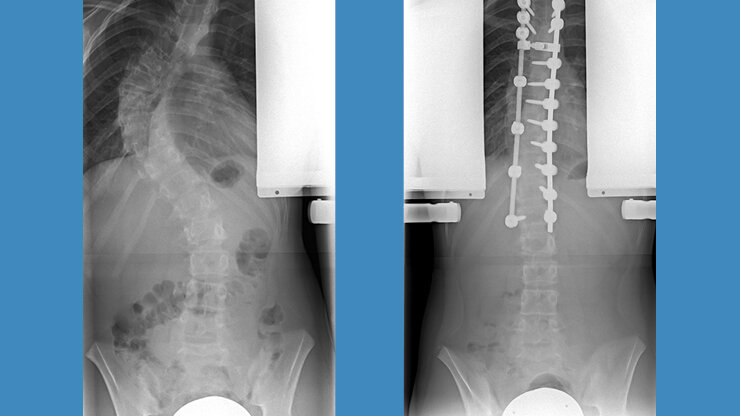

Dorsale Skoliose-Operation

Der Großteil der Skoliosen wird heute von hinten, also dorsal, operiert. Dank moderner Systeme sind ähnlich kurze Operationsstrecken möglich. Patientinnen und Patienten liegen während des Eingriffs auf dem Bauch und die Wirbelsäule wird durch einen mittigen geraden Schnitt freigelegt.

Anschließend werden Schrauben in den Wirbelköpern verankert, an denen die einzelnen Wirbel dann ausgerichtet werden können. Durch neue Techniken mit Schrauben, die auch eine  Drehung (Derotation) der einzelnen Wirbelkörper erlauben, können mittlerweile ähnlich gute Ergebnisse, wie mit der Skoliose-OP von vorn, erzielt werden. Desweitern können von hinten zusätzlich noch die Wirbelgelenke gelöst werden, um die Wirbelsäule flexibler zu machen. Der Rippenbuckel wird durch Osteotomien der Rippen korrigiert und Schmerzkatheter werden entsprechend eingelegt.

Thorakolumbale Krümmung Th 10 bis L3 von dorsal

Thorakale Krümmung Th 3 bis 12 von dorsal